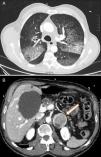

Varón de 68 años que acudió a urgencias tras episodio de hemoptisis franca asociado a dolor torácico opresivo con cortejo vegetativo. En la exploración física se mostraba disneico con sudoración fría y palidez, TA>180/100mmHg, FC 120lpm. El ECG sin alteraciones significativas, radiografía de tórax con patrón alveolar difuso bilateral. En la analítica destacaban: glucemia de 257mg/dl, leucocitosis con neutrofilia, hemoglobina 14g/dl (VCM normal), creatinina 1,19mg/dl, urea 62mg/dl, troponina T 596,6ng/l y CK 186U/l. La gasometría arterial era compatible con insuficiencia respiratoria hipoxémica (PaO2 51,4mmHg). Ante la sospecha de síndrome coronario agudo sin elevación del ST y la hemoptisis se ingresó al paciente en la UCI iniciándose solo doble antiagregación al desestimarse el tratamiento anticoagulante por la hemoptisis. Presentó un nuevo episodio de hemoptisis franca asociado a crisis hipertensiva que precisó oxigenoterapia y tratamiento con bolos de metilprednisolona iv. Se produjo mejoría clínica en horas con normalización de la función renal y anemización (Hb 10,9g/dl). Reinterrogado, el paciente refería cuadros de cefalea, sudoración y palpitaciones con las maniobras de Valsalva. La TAC evidenció patrón pulmonar «en empedrado», consolidaciones en vidrio deslustrado y engrosamiento de septos interlobares, compatible con hemorragia alveolar (fig. 1A) y lesión suprarrenal izquierda heterogénea de 46×40mm (fig. 1B). Los niveles elevados de catecolaminas y metanefrinas en orina (noradrenalina 1.208,4μg/24h, adrenalina 532μg/24h, normetanefrina 5.748,6μg/24h, metanefrina 12.281,6μg/24h) confirmaron el diagnóstico de feocromocitoma. El paciente fue tratado con bloqueadores alfa (fenoxibenzamina: 10mg/8h), asociándose después bloqueador beta (propranolol 10mg/8h). Tras mejoría progresiva en 7 días, se realizó una fibrolaringoscopia que mostró ausencia de sangrado en faringe y laringe y broncoscopia normal. El lavado broncoalveolar evidenció ausencia de células malignas con abundantes hemosiderófagos (>20%). Los anticuerpos anti-DNA, c-ANCA, anti-MPO, anti-GBM y los cultivos fueron negativos. Una vez estabilizado se realizó adrenalectomía izquierda vía laparoscópica, con estudio anatomopatológico de feocromocitoma con rasgos histológicos de malignidad. Durante el seguimiento, el paciente permanece asintomático con normalidad de las pruebas solicitadas (2 meses tras episodio agudo presenta gasometría con PaO2 85mmHg).